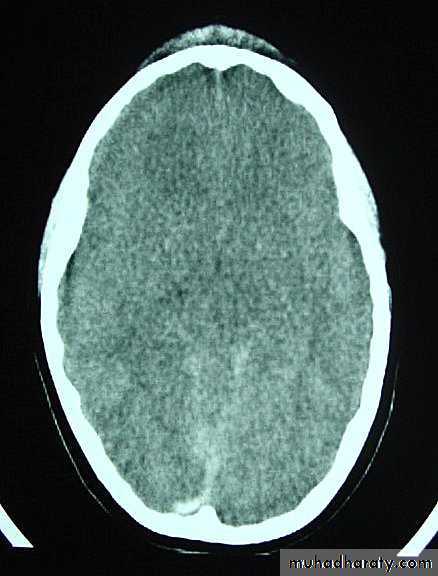

1. Diffuse Axonal Injury

Prolonged post-traumatic state in which there is loss of consciousness from the time of injury that continues beyond 6 hours.Occurs as a result of mechanical shearing at the grey-white matter interface.

This causes disruption and tearing of axons, myelin sheaths and blood capillaries.

Severity can range from mild damage with confusion to coma and even death.